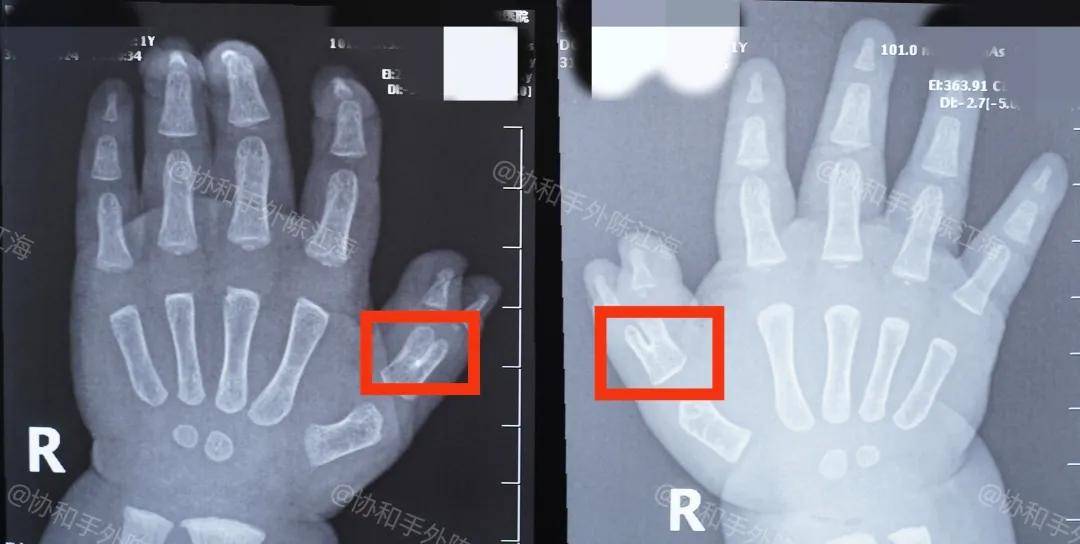

多指、三型多指!

孩子的多指属于是III型,特点是近节指骨有部分的融合以及部分的分叉,所以从外形上来说,两个拇指都会相对偏小,因此在保留一侧的同时,根据孩子的情况考虑要对软组织进行调整,来让它看起来更加的饱满。

术后孩子来复查的时候,也是可以看到孩子右手的指甲与之前相比,并没有明显的弯曲和过小,这也是爸爸妈妈坚持功能锻炼的成果。